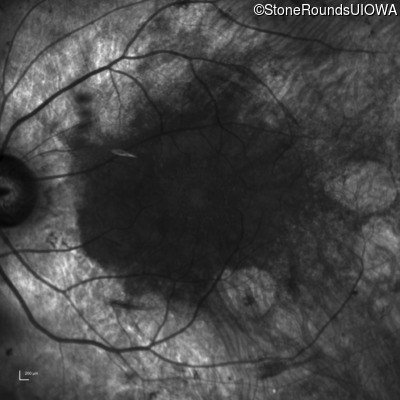

Infrared Fundus Photograph - Right - 20/50

Exemplar